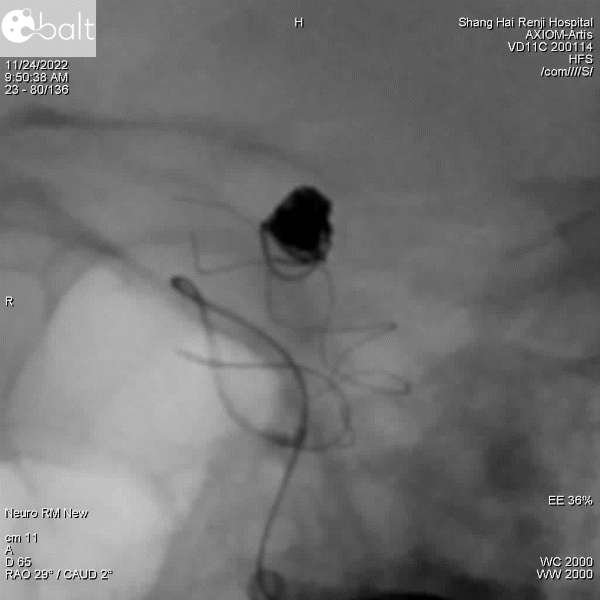

图3:栓塞完毕,支架解脱后造影,动脉瘤不显影。

图4:支架末段卸张力释放,造影提示贴壁欠佳(红色箭头)。

考虑到支架近端已经完全打开,此时可以采用微导丝微导管按摩来让支架完全贴合血管壁。